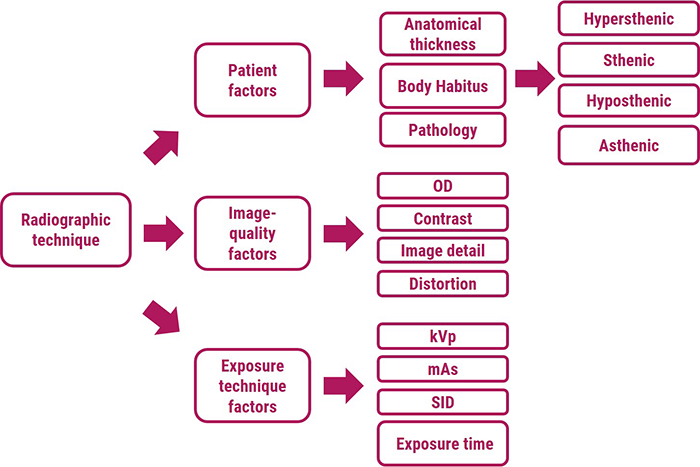

As shown in this diagram, radiographic technique is a combination of different factors used to expose a well-defined anatomical part to produce a high-quality radiographic image.

- Patient factors

- Image-quality factors

- And exposure technique factors

Patient factors include anatomical thickness, body composition, and any pathology that is present. Radiographers recognize sthenic, asthenic, hyposthenic, and hypersthenic body habitus types as a way to determine body composition and thus to select proper radiographic technique. Pathology in the body may be destructive and therefore radiolucent, which requires a reduction in technique, or constructive and therefore radiopaque, which requires an increase in technique.

Image-quality factors include Optical Density (OD), contrast, image detail, and distortion. Optical density, which means blackening of the radiograph, is defined as the log of the incident light over the transmitted light. The Contrast is the difference in the optical density between adjacent anatomical structures. Whereas high kVp produces low-contrast images, low kVp produces high-contrast images. Image detail is the sharpness of the image on the radiograph. To produce the sharpest image detail, the smallest focal Spot, the longest SID (Source – image distance), and the least OID should be used. Distortion shape on the radiograph refers to misrepresentation of object size or shape on the radiograph.

Radiographic exposure factors (kVp, mAs, and SID) are manipulated by radiologic technologists to produce high-quality radiographs. Exposure factors influence radiographic quantity (number of X-ray) and quality number (penetrability of the X-rays). Therefore, proper selection of exposure factors optimizes the spatial contrast resolution of the image.